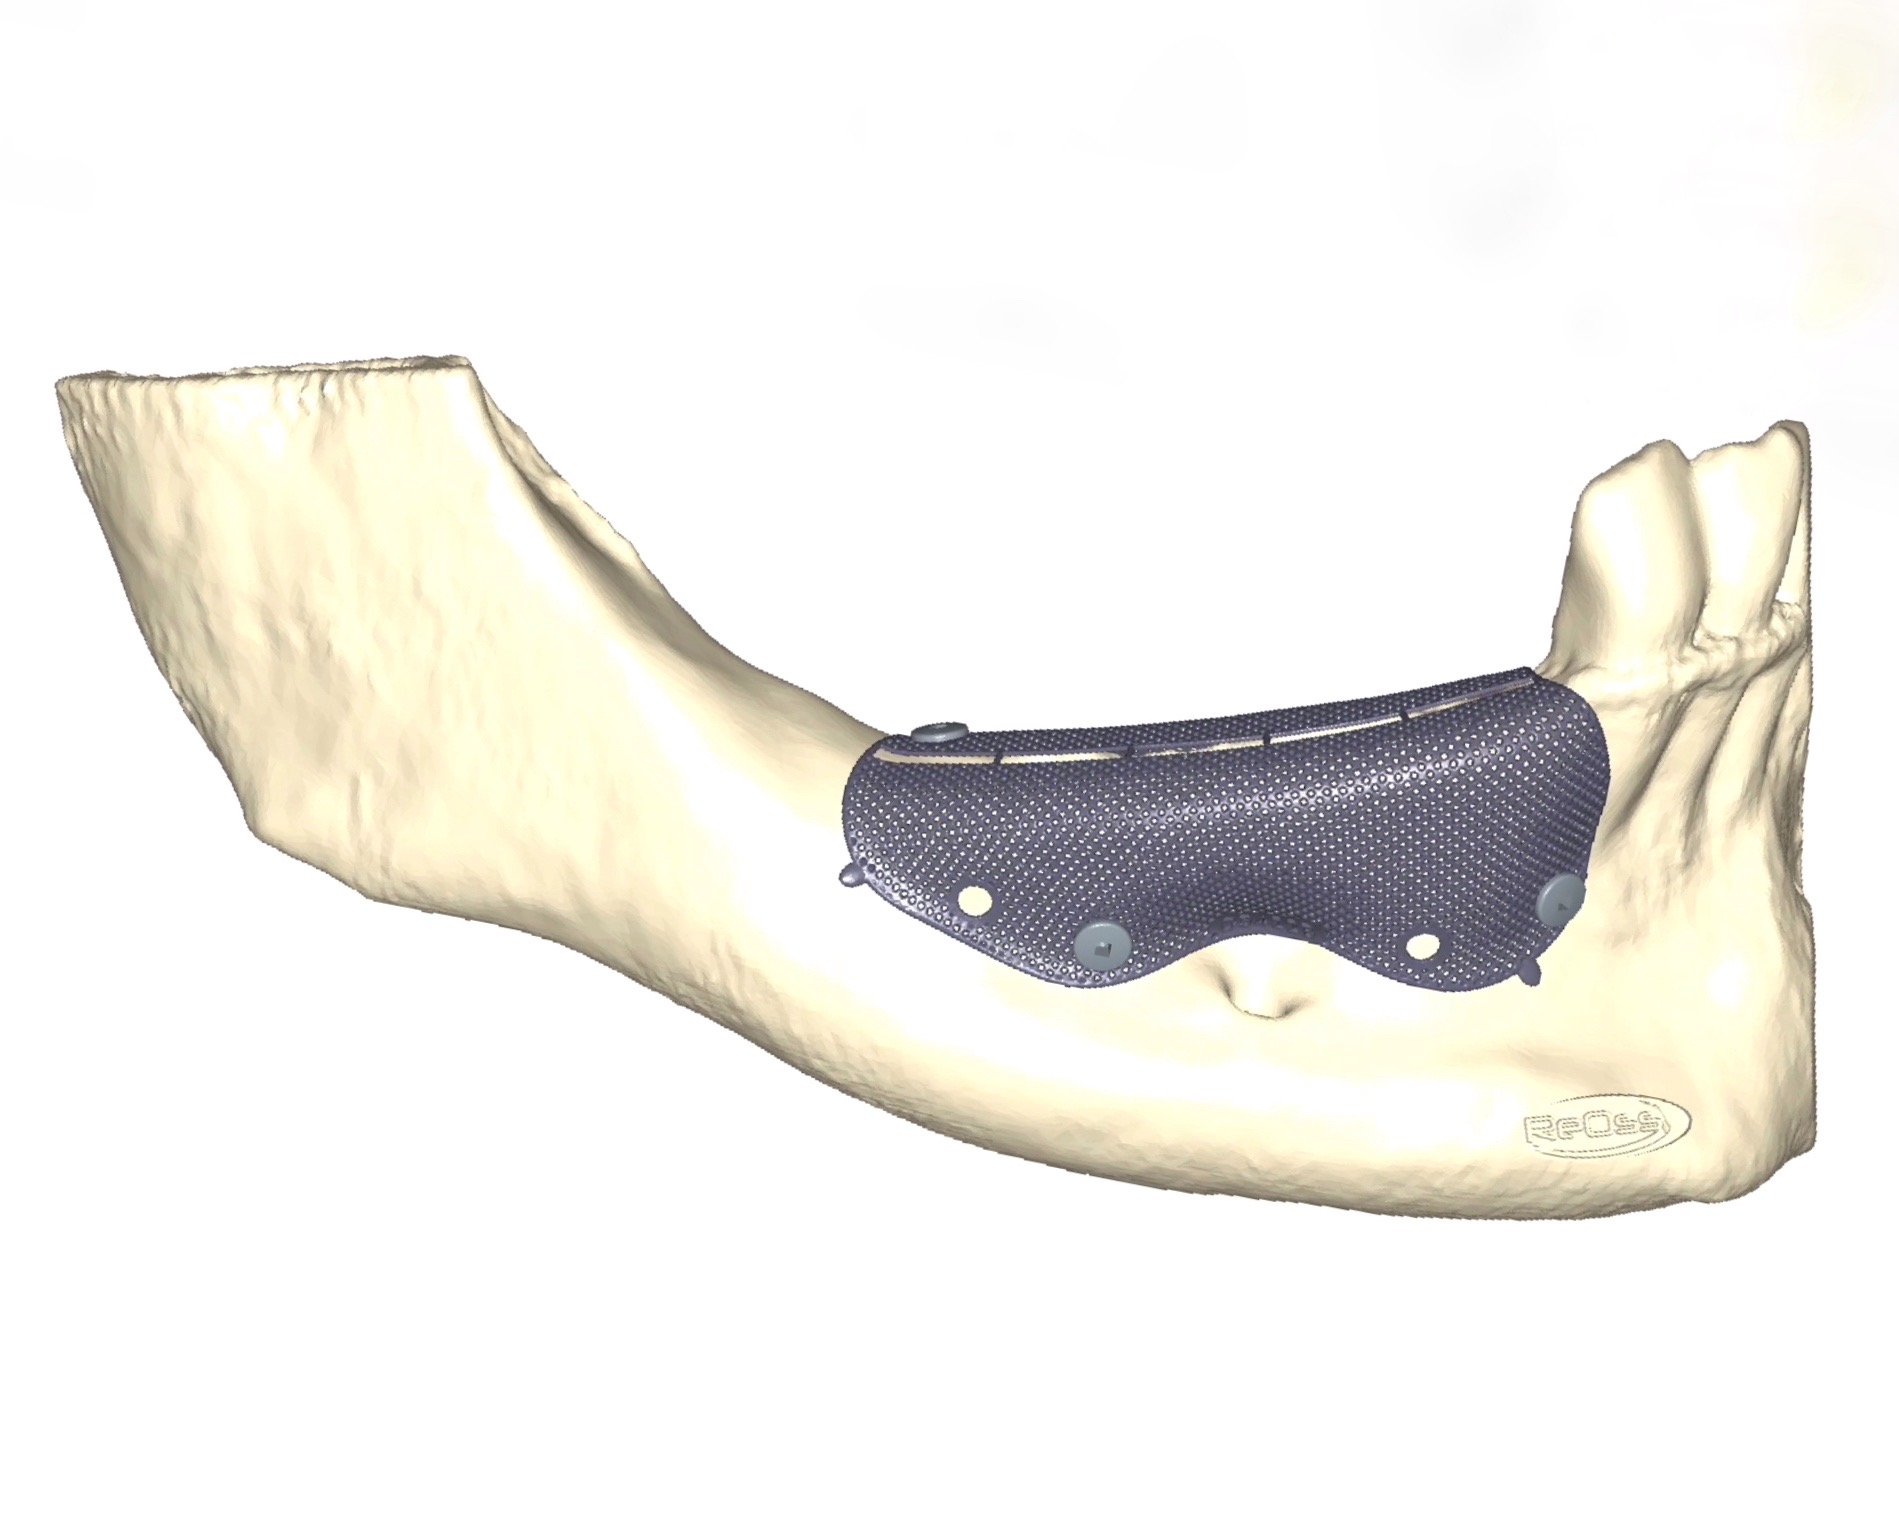

La visualizzazione della CBCT (Figure 2a-b) permette di valutare tridimensionalmente l’atrofia riscontrata durante l’esame clinico. Le immagini ricavate dalla rx evidenziano come l’atrofia sia stata sottostimata rispetto alle aspettative, in quanto la sezione di mandibola mostra un aspetto a lama di coltello con un importante sottosquadro linguale. Prima di poter procedere al posizionamento implantare risulta quindi necessario intervenire con la rigenerazione del volume osseo corretto. Viene pertanto proposta alla paziente una chirurgia rigenerativa realizzata mediante l’ausilio di una griglia customizzata in titanio, realizzata sulla base della ricostruzione tridimensionale ricavata dalla Cone Beam.

In fase preoperatoria si va a produrre, sulla base del file DICOM estratto dalla CBCT, una griglia customizzata in titanio Reoss Yxoss CBR fully-protect (Reoss, Filderstadt, Germania) (Figure 3a-b).